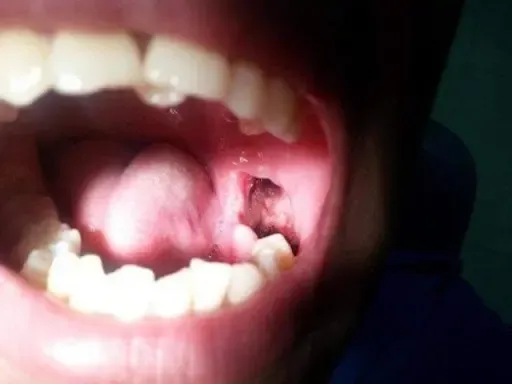

Vết sưng bình thường sẽ mềm và giảm dần. Ngược lại, vết sưng do nhiễm trùng (áp-xe) có đặc điểm:

- Không giảm mà còn lan rộng hơn sang các vùng khác như sàn miệng, dưới cằm, vùng mắt.

- Ấn vào cảm thấy cứng chắc thay vì mềm.

- Da vùng sưng có màu đỏ, căng bóng và nóng ran.

- Có thể gây khó há miệng, khó nuốt hoặc khó thở – đây là những dấu hiệu cực kỳ nguy hiểm.